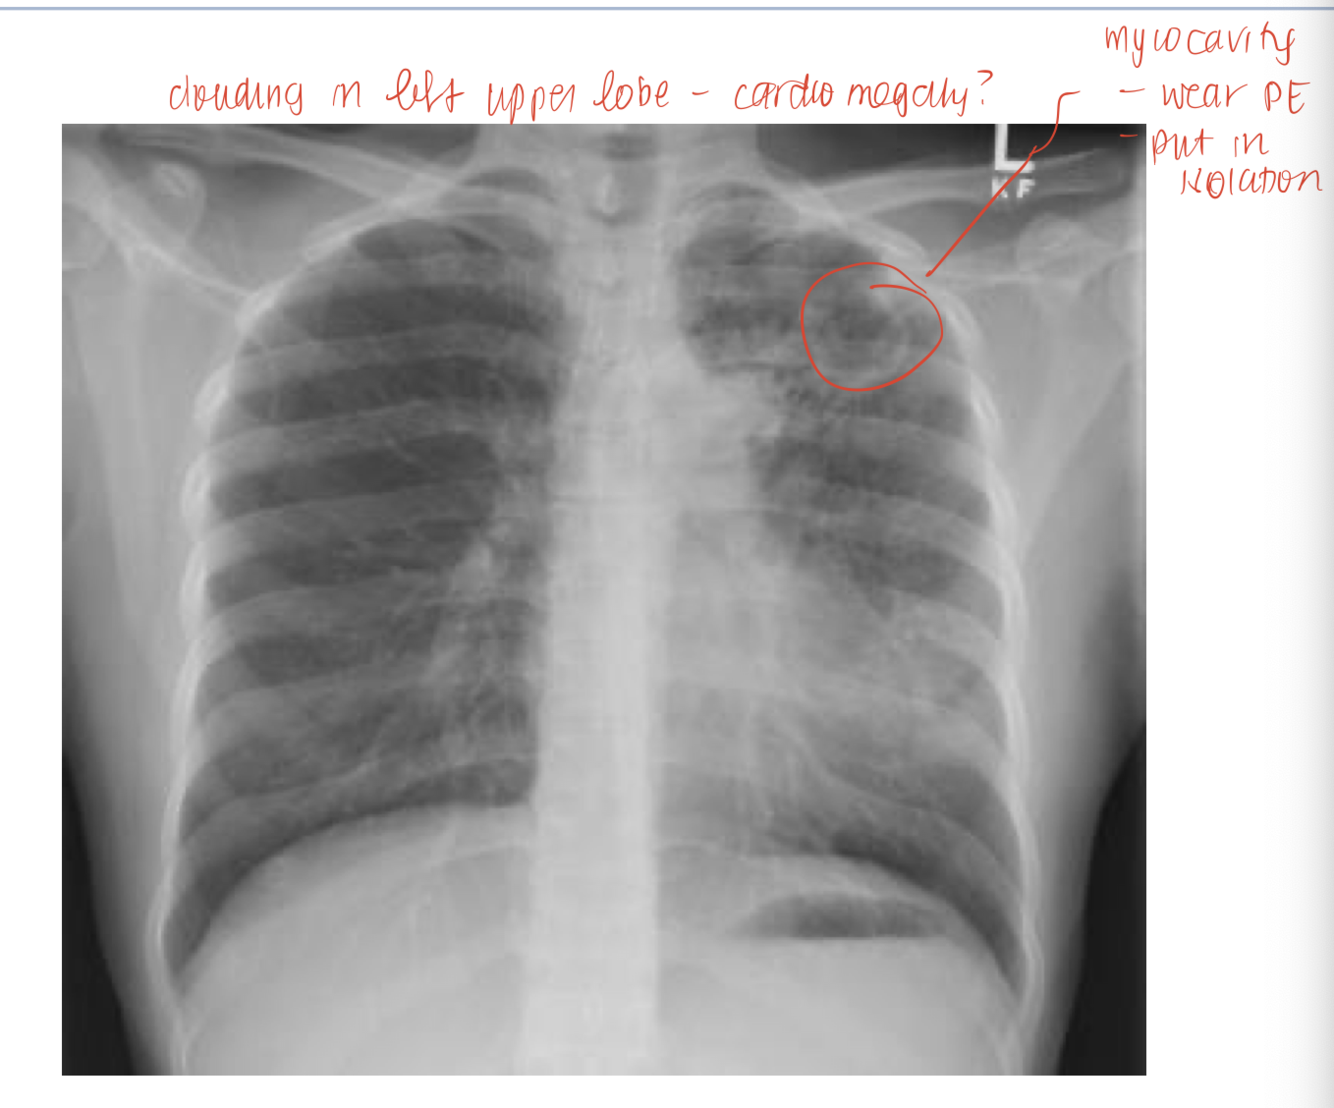

myococavitation

cough, hemotysis, fever, dyspnea, weight loss, night sweats, subacute or chronic presentation. need to do CXR